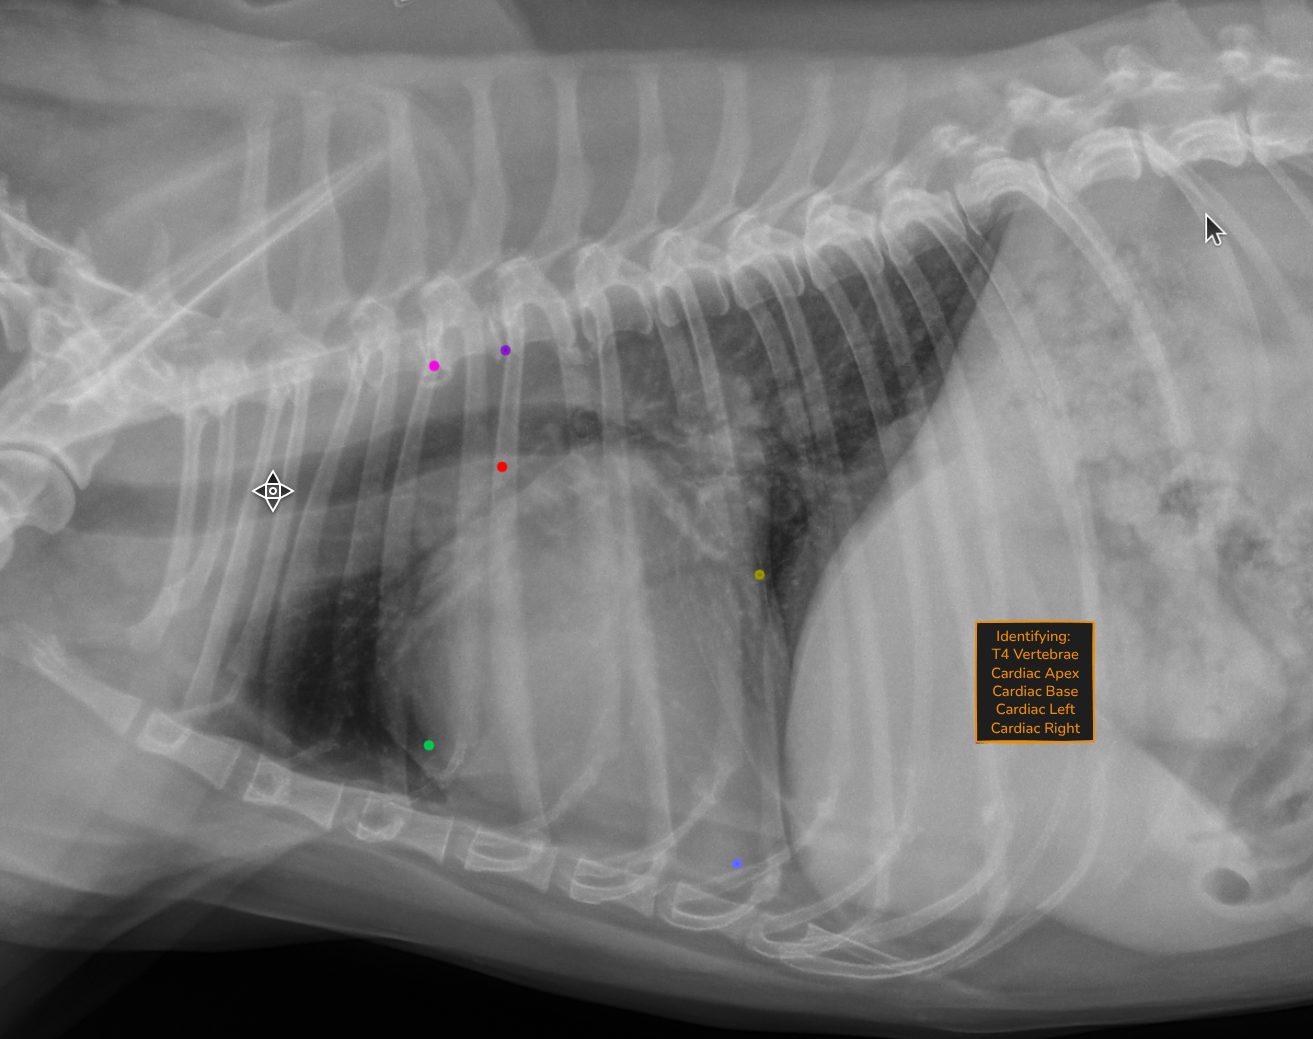

Automated VHS calculation

Vertebral Heart Score is calculated automatically on every lateral thoracic radiograph. The measurement is overlaid directly on the image with vertebral reference lines, so you can verify it at a glance.

No more manual measurement. No more variability between reads. Just a consistent, repeatable number ready for your interpretation.

AI identifies cardiac landmarks on the lateral thoracic radiograph.